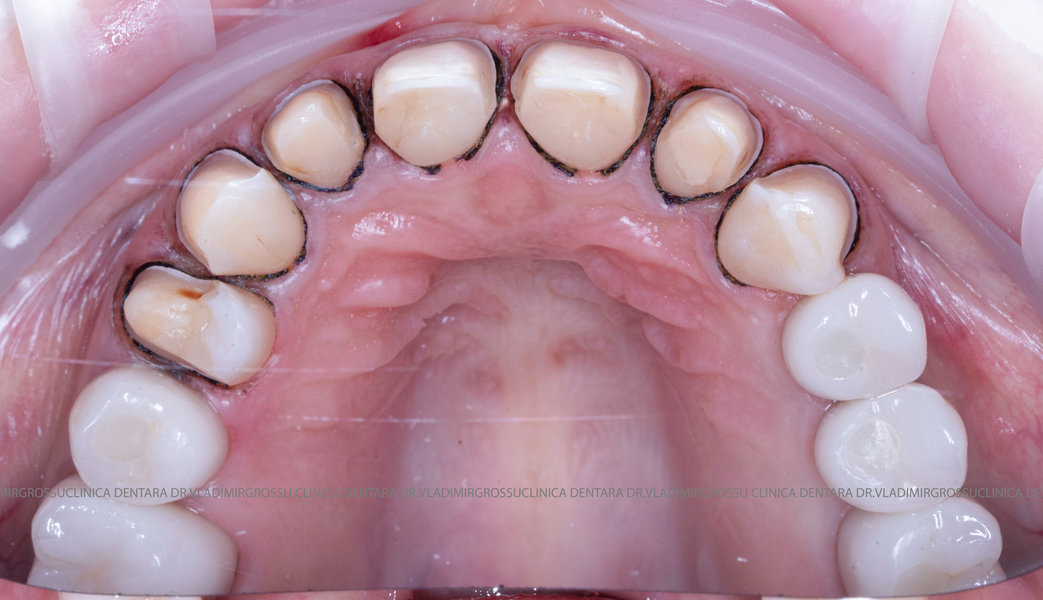

Caz 1

Tomografii (CBCT)